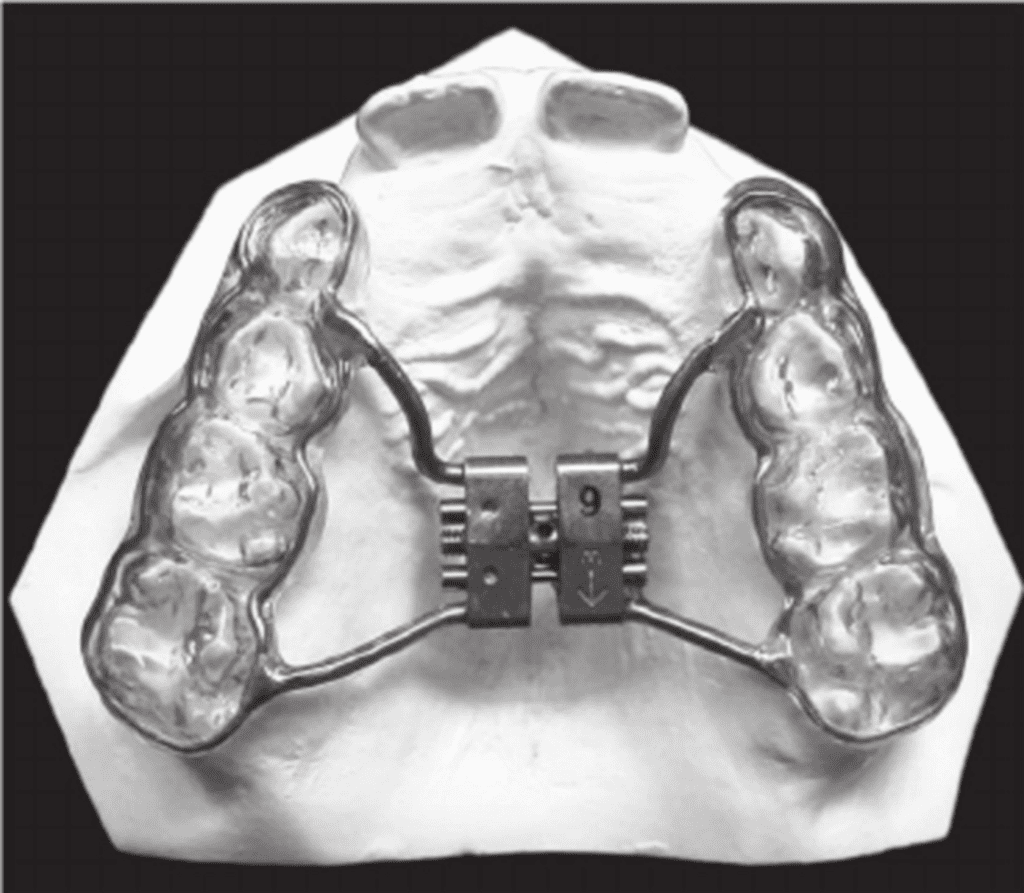

Biedermann type: It was introduced by Willian Biedermann in 1968. This tooth-borne appliance uses a HYRAX (hygienic rapid expansion) screw, named after the ability to keep it clean. The screw has heavy wire extensions, which can be adapted to follow the contour of the palate and are soldered to either metal bands or cast cap splints or a wire framework that has acrylic splints or is embedded in acrylic splints.

The expansion screw is turned with a key either once or twice daily (0.2 mm expansion/turn) for the entire expansion phase of treatment which usually lasts from 2-4 weeks. It is capable of providing sutural expansion of 11mm within a very short period of wear and a maximum of 13mm can also be achieved. RPE utilizes large forces to produce maximal orthopaedic repositioning with a minimum of orthodontic movement.

Technique for SARME– Hyrax expander is cemented onto the maxillary first molars and premolars before the surgical treatment, which includes bilateral osteotomies performed from the piriform rims to the pterygomaxillary junction. A screw expansion of approximately 2 mm is performed directly after surgery, and the screw is then activated once or twice a day until the desired expansion has been achieved.